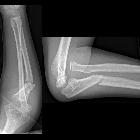

Preschooler

with forearm pain after a fall. AP and lateral radiographs of the elbow show a fracture of the ulnar diaphysis and a dislocation of the radial head.The diagnosis was a Monteggia fracture dislocation.